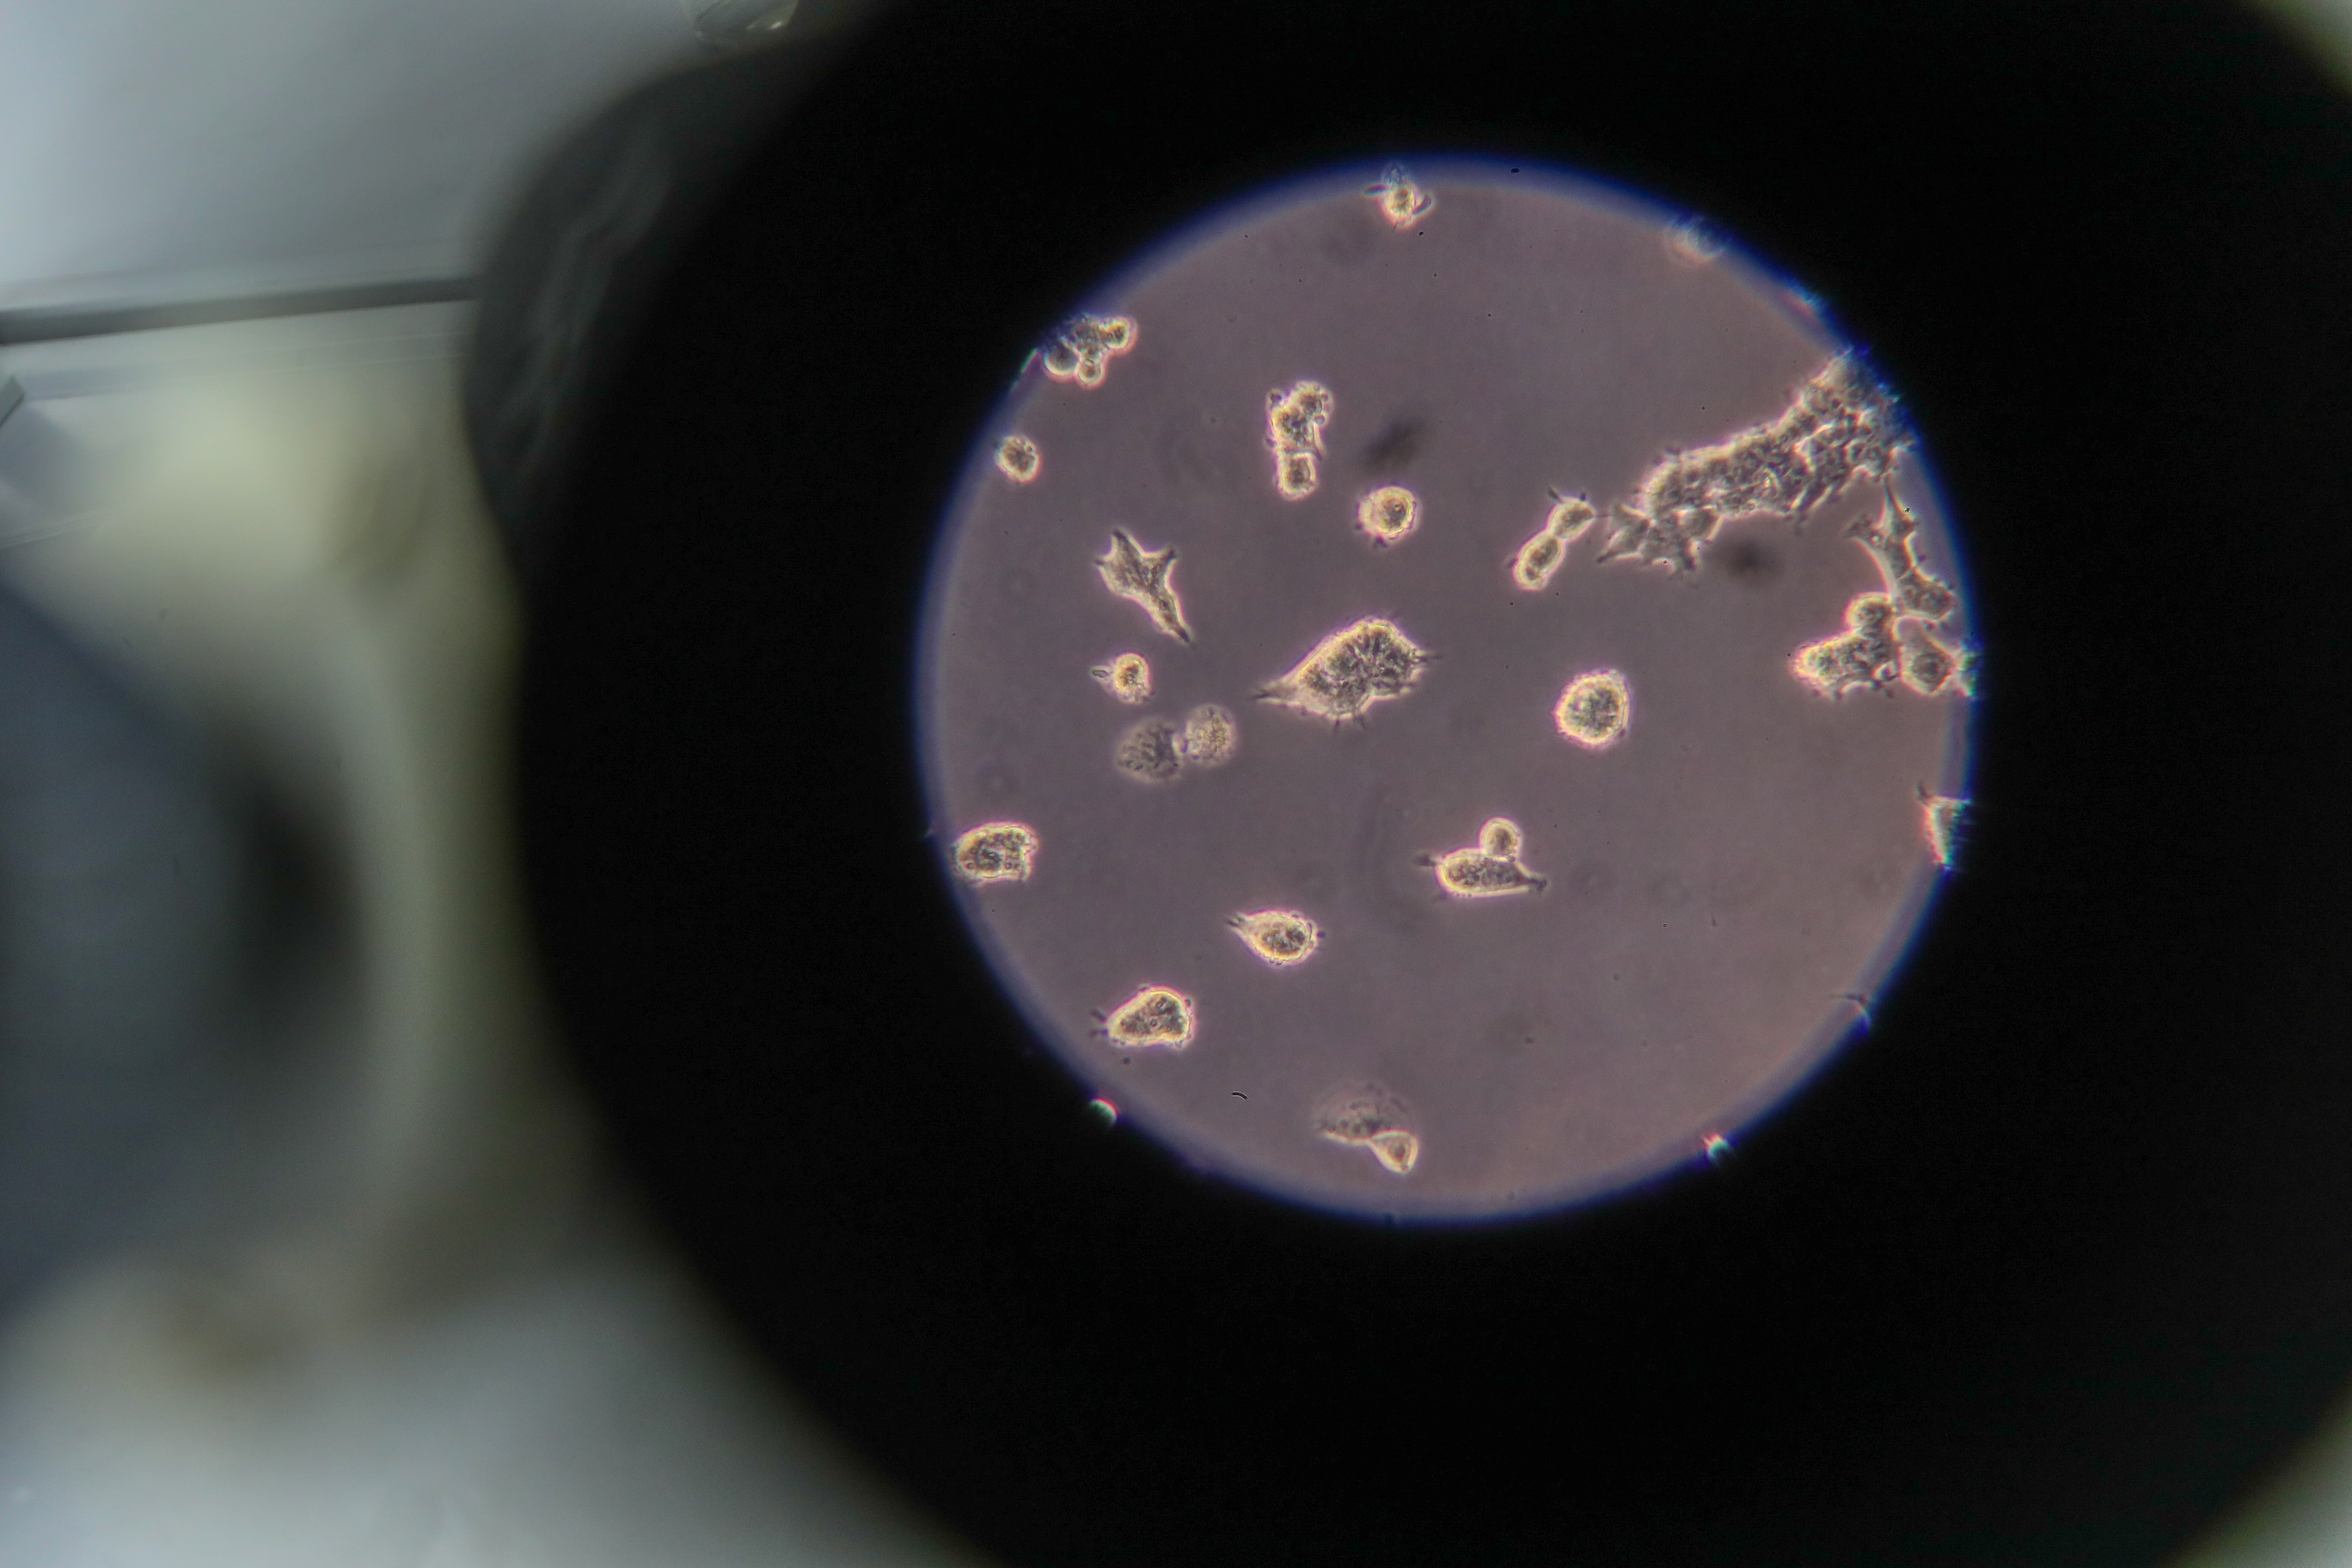

MOSCOW, February 1. /TASS/. Russia’s Sistema-BioTech, a subsidiary of the Sistema Joint Stock Financial Corporation, confirmed the possibility of detection of mutated SARS-CoV-2 coronavirus strains, including the British one, using previously developed test systems, the company announced Monday.

"A research we’ve conducted has confirmed the possibility of detection of the mutated coronavirus strains, including the British one, as well as others, using the test systems, developed by Sistema-BioTech," the company said.

The first test system is a set of chemical substances for detection of the causative agent’s RNA via the PCR method in real time. Besides, the company has two express tests that can reduce the reaction time to less than half an hour. One such test is designed for use in a standard diagnostics lab, while another one is colorimetric, making it possible to detect the presence of the virus by change of color of a liquid in a test tube - for example, directly at a patient’s bed.

The company explained that the tests seek for the 3CL proteinase gene, which is the least likely gene to mutate. For example, the British coronavirus strain has this gene unchanged despite the 23 accumulated mutations in other genes. Therefore, Sistema-Biotech’s PCR tests can efficiently detect the coronavirus infection despite the mutations.

According to the company, its specialists analyzed a wide spectrum of related viruses, including the 2003 atypical pneumonia causative agent, and concluded that a mutation in the 3CL proteinase gene is usually lethal for the viruses.

"Therefore, it remains unchanged, and a test system that aims at it, will be at advantage in case of a prolonged pandemic," Sistema-BioTech Director on Science Natalya Pozdnyakova said.

The UK coronavirus strain, revealed on December 14, 2020, is believed to be 70% more virulent than the previous variant.